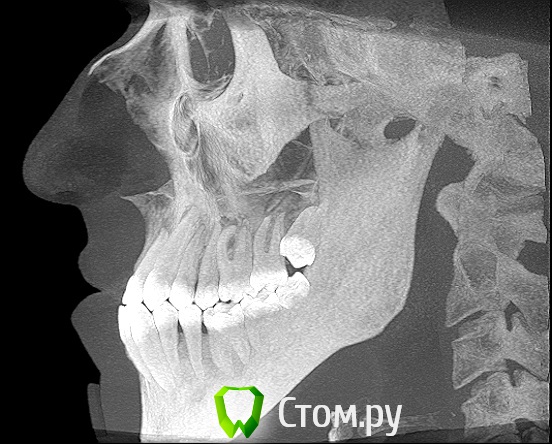

Здравствуйте! Мне 27 лет.  Очень вас прошу дать свою оценку моей ситуации. У меня сложная ситуация, я уже обошел многие ортодонтические кабинеты своего города и все говорят разное. У меня мезальный прикус, но своим профилем я доволен, я всем доволен, кроме того что у меня неправильный прикус (верхние резцы заходили за нижние и были вогнуты вовнутрь) и кривые зубки.Сейчас по рекомендации одного ортодонта ношу капу чтобы верхние резцы перепрыгнули, но теперь и это занятие меня сильно беспокоит, хотя ношу всего месяц и уже попадает зуб на зуб. Главный мой вопрос таков: "Возможно ли в моей ситуации исправить прикус без операции?" Спасибо за ответы!

можно, еще ТРГ надо,